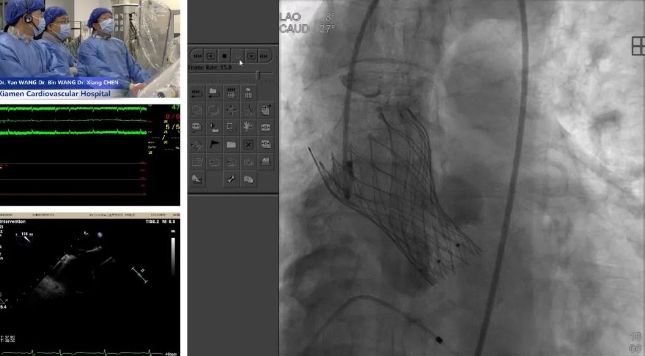

2024-12-18一天两场国际手术直播,厦心医院助力国产创新器械出海 -